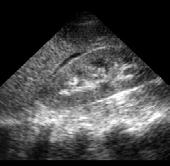

Principalele instrumente de care medicul radiolog dispune în prezent în evaluarea pacientului cu cancer rectal sunt ultrasonografia endorectală (ERUS), tomografia computerizată (CT) și imagistica prin rezonanță magnetică (IRM). În prezent, cel mai adesea este folosită o combinație între ultimele două.

Rolul CT-ului în managementul cancerului rectal

Tomografia computerizată (CT) este una dintre primele investigații imagistice recomandate după confirmarea diagnosticului de cancer rectal. Aceasta poate oferi și unele informații despre invazia tumorală locală, dar rolul ei principal astăzi constă în evaluarea extensiei la distanță a bolii, fiind excelentă pentru identificarea metastazelor pulmonare și hepatice. CTul permite o evaluare rapidă și detaliată a cavității abdominale și toracice, având un rol cheie în stadializarea TNM (Tumor, Node, Metastasis) a cancerului.

Metastaze pulmonare. Examen CT multislice, fereastră pulmonară, plan axial.

Din colecția Centrului de Imagistică, UMFCV